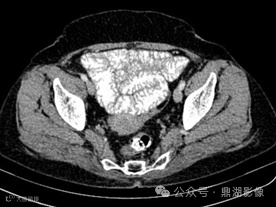

患者,女,55岁,长期腹泻、体重减轻和缺铁性贫血。

口服造影剂后CT平扫

CT小肠造影显示回肠袢轻度扩张,回肠皱襞增多、空肠皱襞减少,并伴有多个肠系膜淋巴结肿大。未发现肠套叠、狭窄或肿块形成等征象。

空回肠皱襞模式反转

空回肠皱襞模式反转(称为回肠空肠化,空肠皱襞减少,回肠皱襞增加)是乳糜泻最特异的征象,文献报道其敏感性和特异性(阳性预测值和阴性预测值)接近100% 。 5cm距离内回肠皱襞数量多于空肠皱襞数量时,则被认为是阳性。

CT和MR小肠造影中,空回肠皱襞模式反转和肠系膜淋巴结肿大是乳糜泻的特征性表现。疾病的严重程度差异极大,从节段性受累到弥漫性小肠受累不等,但最常累及近端空肠。

在CT和MR小肠造影图像上观察到每英寸(=2.54cm)肠段的皱襞少于或等于3个,则认为空肠皱襞密度降低。在重度乳糜泻中,空肠皱襞可能完全消失。在慢性炎症的情况下,回肠皱襞密度可能代偿性增加,定义为每英寸超过5个皱襞,以增加小肠表面积。皱襞数量的增加代表回肠对空肠吸收能力下降的一种适应。